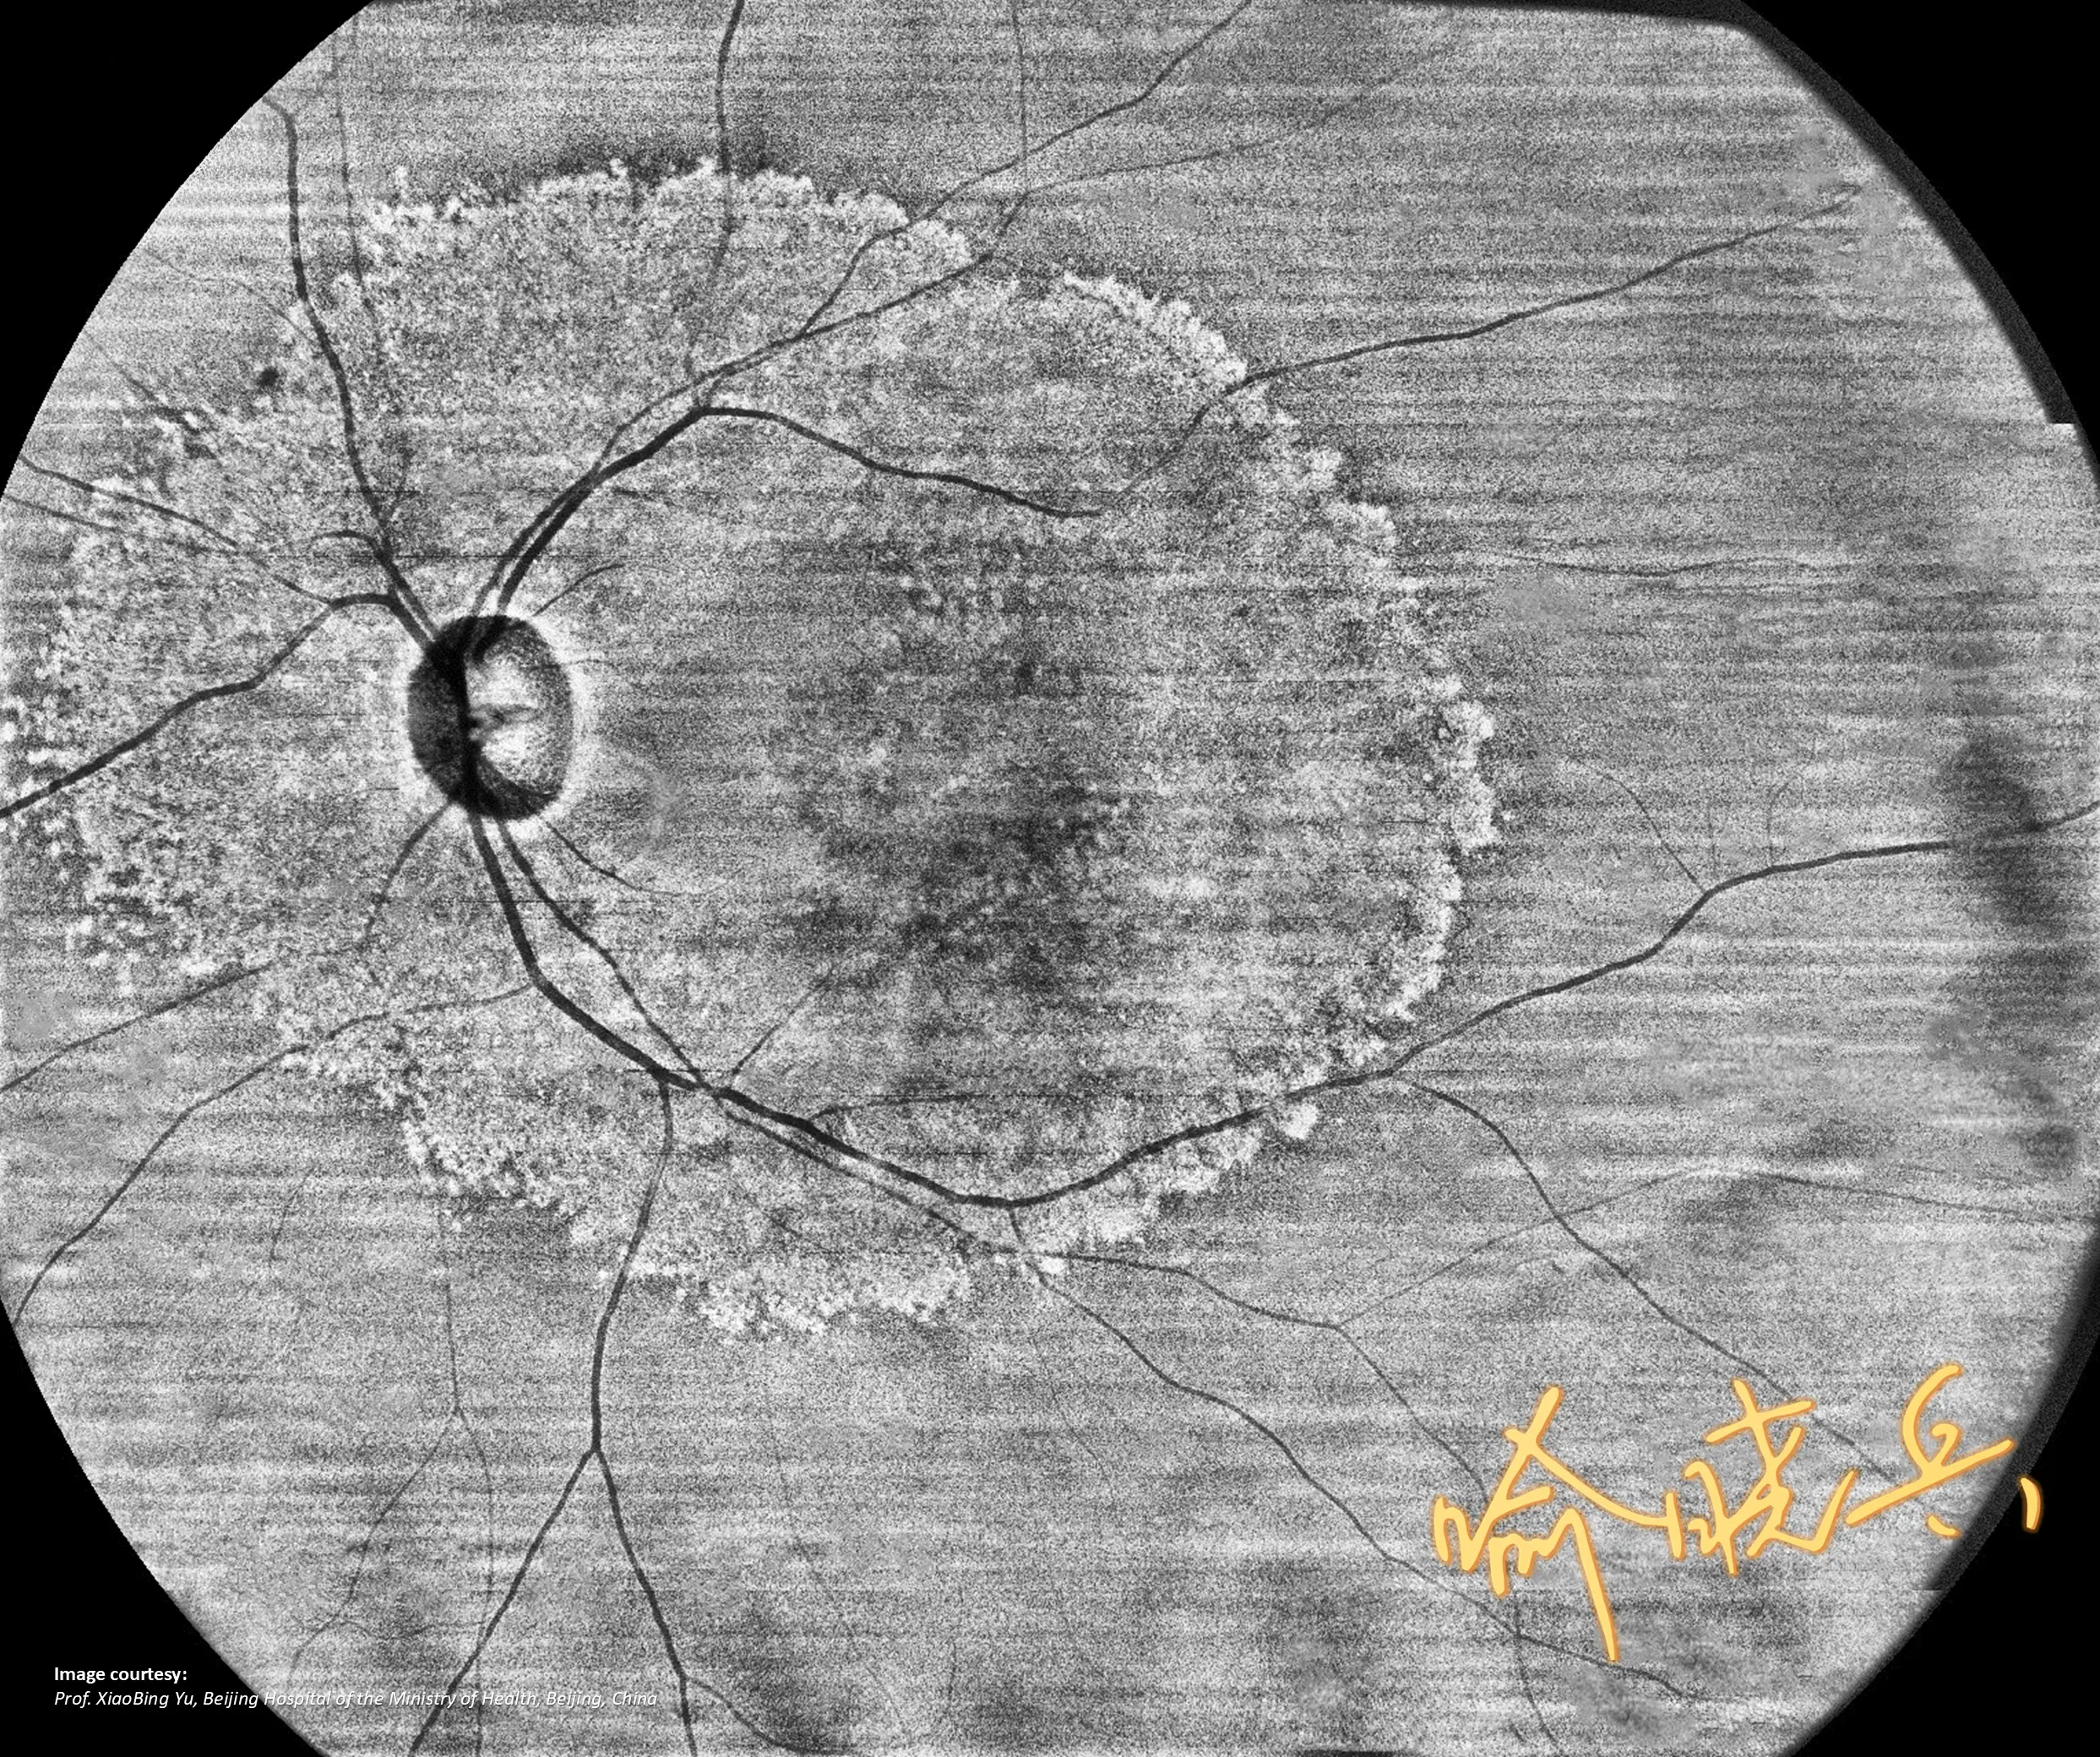

Full-range SS-OCT YAlkaid skanuje jednocześnie przedni i tylny segment oka w jednym badaniu, a BMizar umożliwia ultra-szerokokątne pole 24×20 mm, co pozwala wykryć zmiany obwodowe.

Oba urządzenia obsługują zarówno OCT, jak i OCTA, oferując algorytmy AI do automatycznej segmentacji warstw, analizę ilościową naczyń oraz 3D-rekonstrukcję. To kompleksowe narzędzia diagnostyczne.

GALERIA PRZYPADKÓW

Kliniczne znaczenie

innowacji